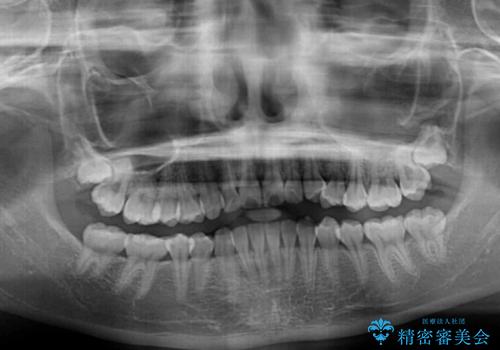

- 前歯のデコボコと磨きにくい奥歯を気にして来院された患者様です。

左右ともに上顎第二大臼歯が外側に転位しており、大変磨きにくくなっているため、補助装置により内側に引き込むことで改善することとしました。

外側を向いていた奥歯は比較的早い時期に歯列に収まり、咬み合わせも磨きやすさも改善することができました。